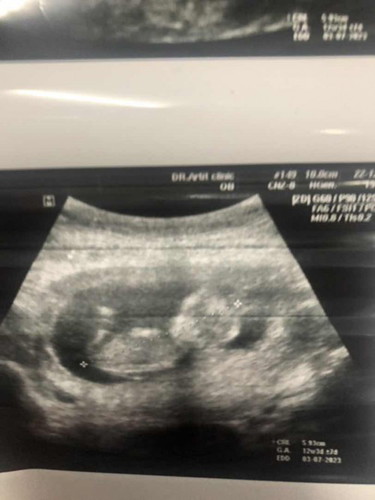

เเม่ๆช่วยดูเพศช่วยหน่อยค้า

13wในรูปน้องอ้าขา พอจะดูเพศออกยังค่ะ

ถ้ามุมนี้ยังมองไม่เห็นค่ะ ของเราน้องอ้ามุมนี้เห็นติ่งชายชัดเลยค่ะ ตรวจ nipt ก็ชาย 😍

ไม่เห็นค่ะ น้องบิดหนี